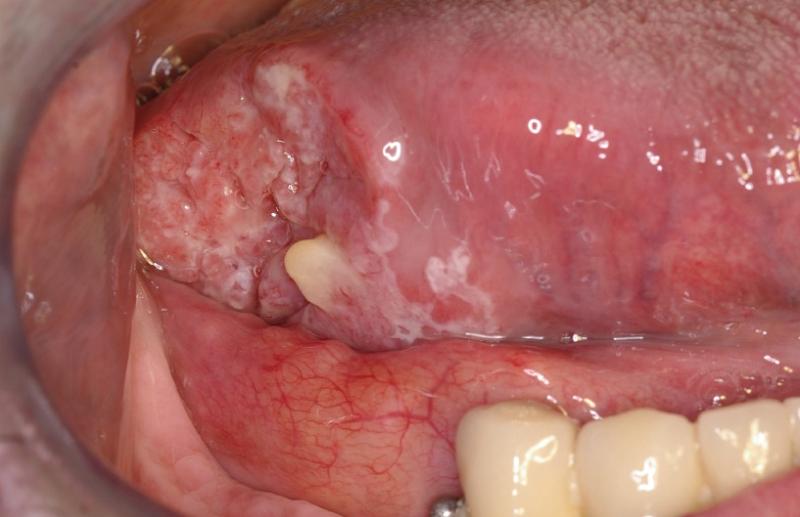

Descripción del caso Un varón de 57 años refiere que hace seis meses empezó a sentir molestias en el lado derecho de la lengua, que han ido en aumento y actualmente le...